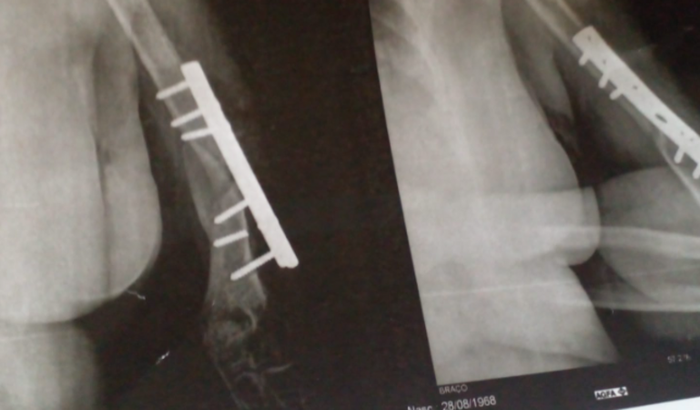

Eu sou aline,estou pedindo ajuda a quem puder ajudar na cirurgia de troca de platina da minha mãe helia gomes de lima,a mesma custa 9,000,pois o pino que segura a platina quebrou dentro do braço dela,precisando ser feita uma cirugia de troca.